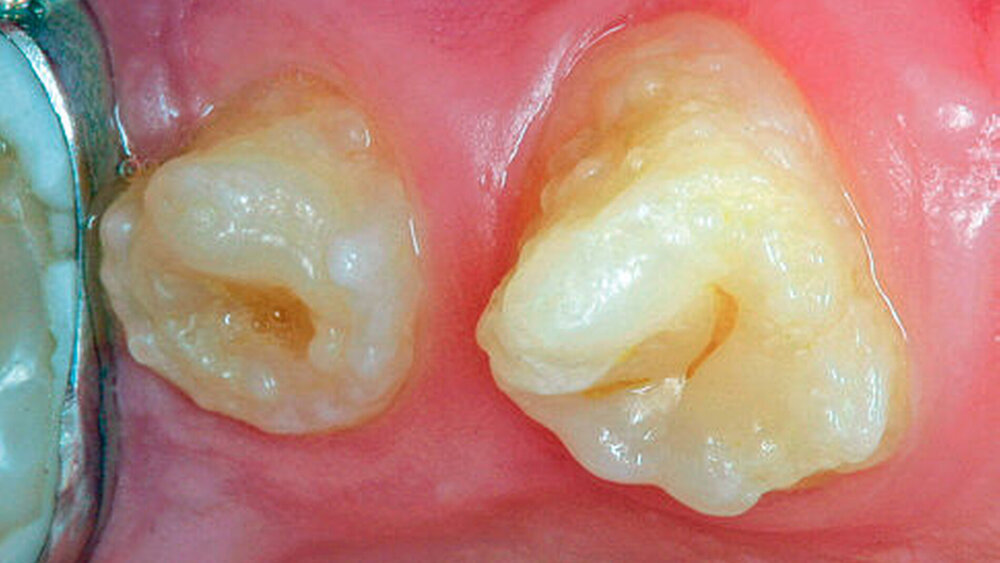

Bei dieser genetisch bedingten Schmelzdysplasie sind in der Regel alle Zähne einer oder beider Dentitionen betroffen, und es ist ein bilateralsymmetrisches Erscheinungsbild vorhanden. Die Ausprägung der Schmelzdefekte kann von Zahn zu Zahn und von Generation zu Generation variieren (Abbildungen 1a bis 1c). Die Struktur des Dentins ist nicht verändert. Die Schmelzdefekte treten als Grübchen von unterschiedlicher Größe in mehr oder weniger normal dickem Schmelz in Erscheinung (Abbildung 2a). Durch Einlagerung von Farbstoffen in diese Grübchen können die Schmelzveränderungen ästhetisch störend wirken (Abbildung 2b). Ähnliche grübchenartige Schmelzhypoplasien können bei Patienten mit Rachitis, Pseudohypoparathyroidismus oder Epidermolysis bullosa beobachtet werden. Bei der hypoplastischen Form der Amelogenesis imperfecta ist die Schmelzhärte normal, die Schmelzdicke jedoch reduziert. Der grübchenartige Typ weist als Ausnahme eine fast normale Schmelzdicke auf (Abbildungen 3 und 4).

Die Amelogenesis imperfecta kann neben der hypoplastischen Form in eine hypomaturierte Form und eine hypokalzifizierte Form eingeteilt werden. Auch Kombinationen der verschiedenen Formen der Amelogenesis imperfecta wurden beschrieben. Bei der hypomaturierten Form ist die Schmelzhärte weicher als normal, die Schmelzdicke entspricht beim Durchbruch der Zähne der Norm. Bei der hypokalzifizierten Form ist der Schmelz sehr weich und die Schmelzdicke beim Zahndurchbruch normal. Deshalb sind vor allem bei der hypomaturierten und hypokalzifizierten Form die Abrasion und Attrition stark erhöht. Bei beiden Formen ist die Zahnfarbe beim Durchbruch der Zähne opakweiß bis gelblich. Mit zunehmendem Alter werden die Zähne braun. Die Prävalenz der Amelogenesis imperfecta beträgt je nach Population und Typ zwischen 1: 700 bis 1 : 20.000.